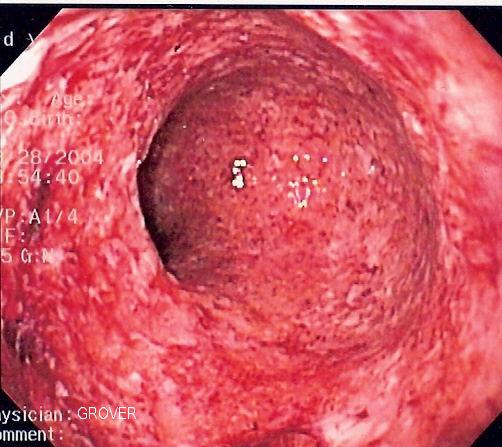

Wer an einer chronisch entzündlichen Darmerkrankung (CED) leidet, sollte jährlich zur Darmspiegelung (Koloskopie).

Diese Patienten haben ein erhöhtes Risiko für kolorektale Karzinome (Dick-/Enddarmkrebs)

Durch die chronische Entzündung und oftmals auch durch die begleitende immunsuppressive Therapie, welche das körpereigene Immunsystem unterdrückt, so dass sich die Autoimmunerkrankungen im Rahmen hält, wird die Tumorüberwachungsleistung des Immunsystems deutlich geschädigt.